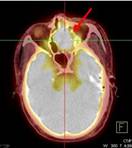

Ca lâm sàng 2: Bệnh nhân Nguyễn T.V., nữ, 72 tuổi. Chẩn đoán: U lympho ác tính không Hodgkin biểu hiện tại phổi, GPB: WF6. Hình CT và PET/CT cho thấy khối u phổi trái tăng hấp thu FDG (vòng tròn) với max SUV=7,94.